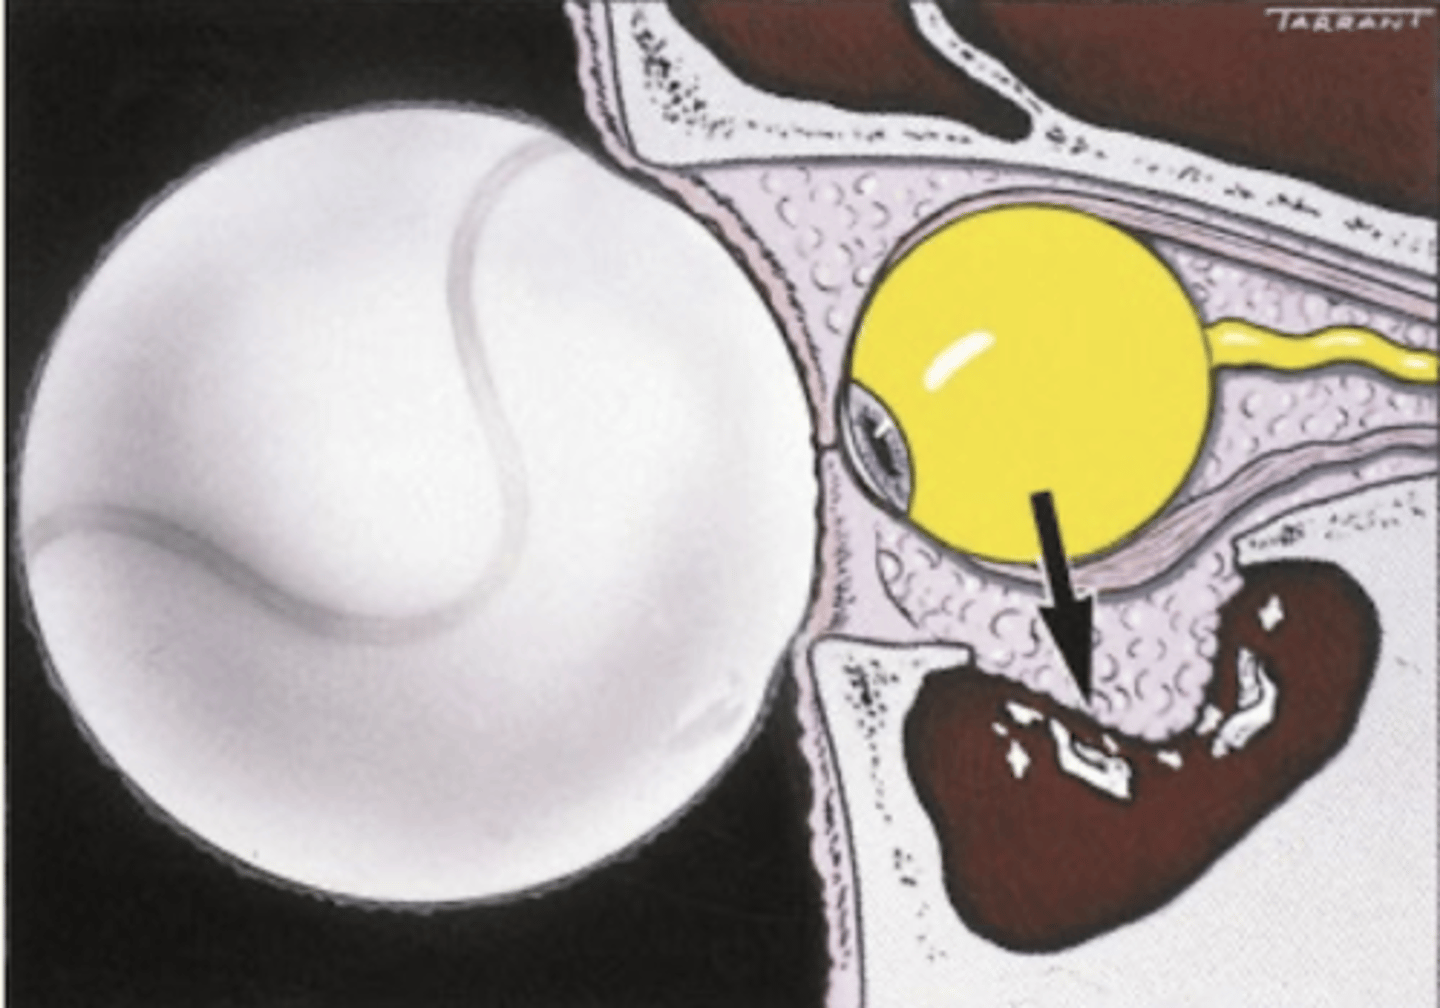

What is an intraocular foreign body?

foreign body in globe

What causes an intraocular foreign body?

metal from metal tasks

What is the presentation of a scleral entry intraocular foreign body?

depends on entry and foreign body:

1. scleral - may lead to deep anterior chamber

2. corneal - corneal edema & a positive Seidel sign

3. iris - transillumination defect & heterochromia

What is the presentation of a corneal entry intraocular foreign body?

corneal edema @ entry site

+ or - Seidel sign

What is the presentation of iris entry intraocular foreign body?

transillumination

heterochromia

peaked pupil (peaked toward entry site)

What is the presentation of EOM entry intraocular foreign body?

restriction

What is the presentation of an anterior chamber entry (corneal) intraocular foreign body?

focal corneal edema over foreign body

What is the presentation of a lens entry intraocular foreign body?

focal lens opacities

What is the presentation of a retinal entry intraocular foreign body?

FB rests on retina

What is the workup for an intraocular foreign body?

CT or MRI (no MRI if metallic!)

What is the treatment for intraocular foreign body?

1. FB removed within 24 hours

2. systemic abx

3. surgical removal